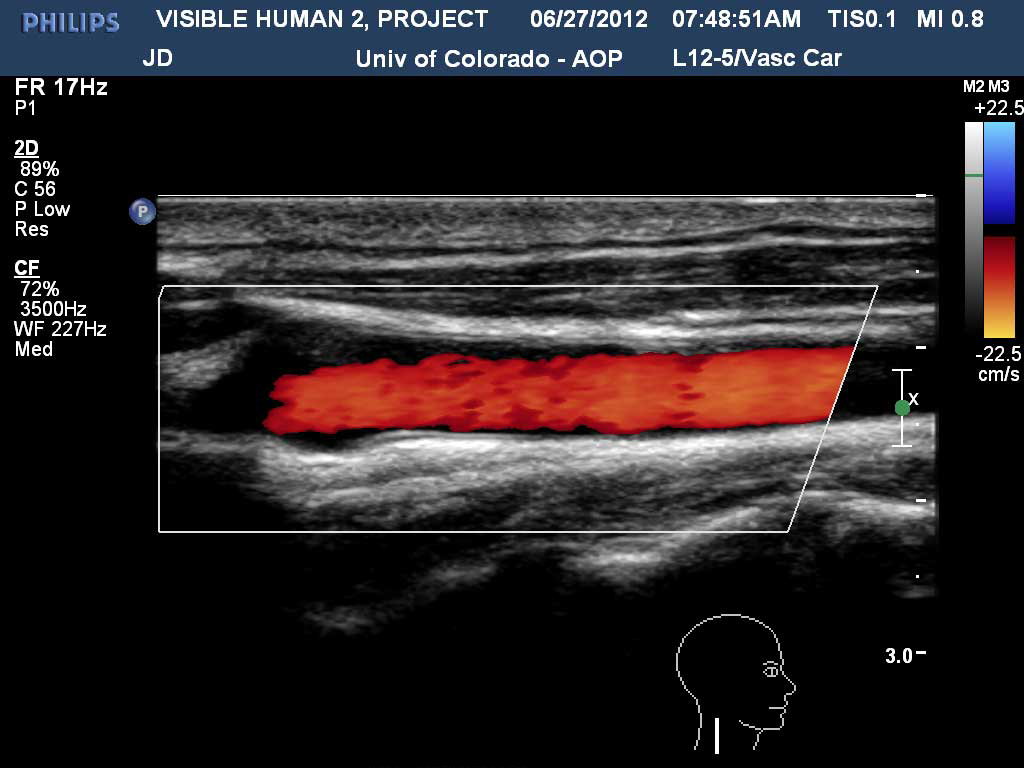

Right Carotid with Doppler

Carotid Artery